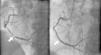

On physical exam, heart rate was 102 beats/min and blood pressure was 103/87 mmHg. The rest of the clinical exam was unremarkable with normal S1, S2 and no murmur. The ECG revealed sinus rhythm, left axis deviation, non-specific intraventricular conduction block and ST-T wave abnormalities suggestive of inferior ischemia. Laboratory tests revealed an elevated troponin I level of 11.8 ng/ml. A two-dimensional (2D) echocardiogram showed severe inferior wall hypokinesis, with moderately reduced left ventricular systolic function and estimated ejection fraction of 35–40%, with no significant mitral regurgitation (MR). The patient was urgently taken to the cardiac catheterization laboratory and was found to have a 99% RCA lesion (Figure 1), with no significant lesions in the other vessels. Successful percutaneous coronary intervention with stenting of the RCA was performed (Figure 1); the patient was admitted to the telemetry floor for close monitoring, and continued on intravenous normal saline to prevent contrast-induced nephropathy.

Figure 1.

Angiography of the right coronary artery, with images before and after percutaneous coronary intervention (white arrow).